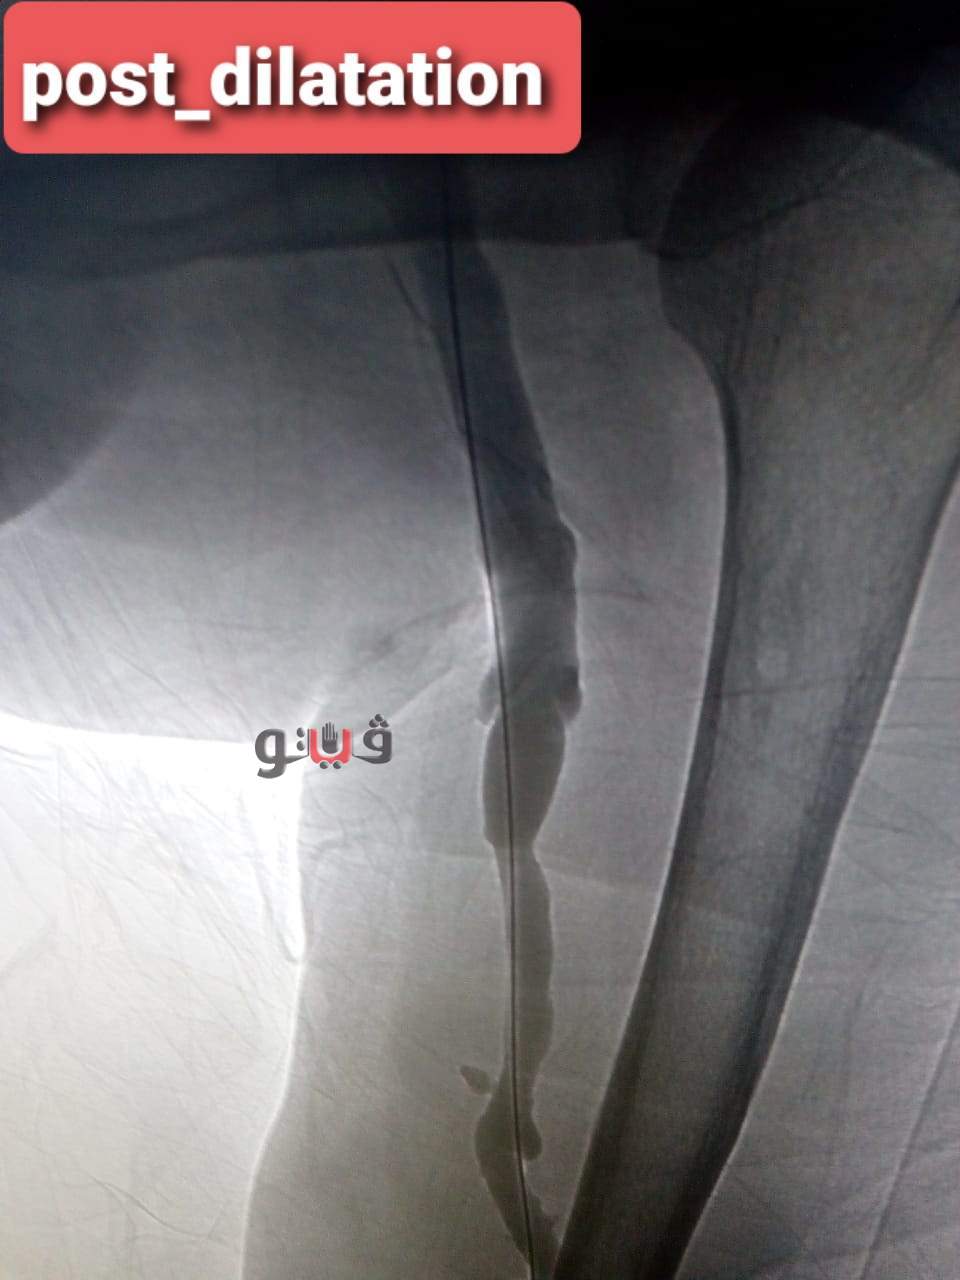

وتمكن الفريق الطبي من استقبال المريضة وعمل قسطرة تشخيصية وتصوير اوردة الذراع الايسر كما تم عمل تدخل علاجي بالقسطرة عن طريق توسيع الوصلة باستخدام البالونات عالية الضغط حيث تم توسيع الوصلة بنجاح .